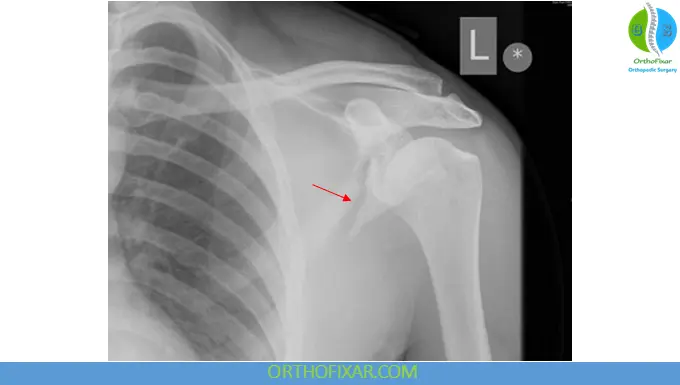

Radiographic Evaluation

Initial imaging:

- Often first detected on chest X-ray

- Standard trauma shoulder series:

- Anteroposterior (AP) view

- Axillary view

- Scapular-Y view